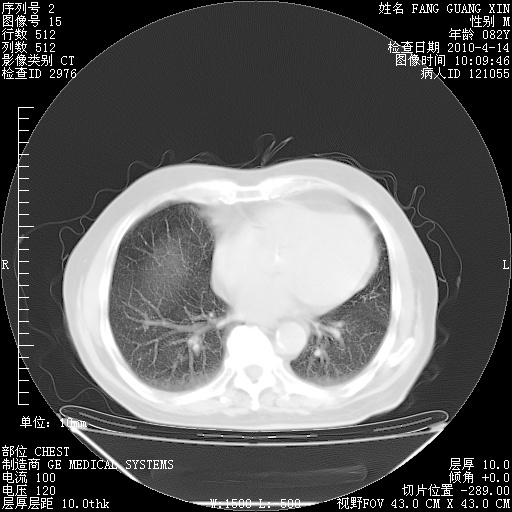

4月14日肺部CT

肺部CT平扫未见异常。